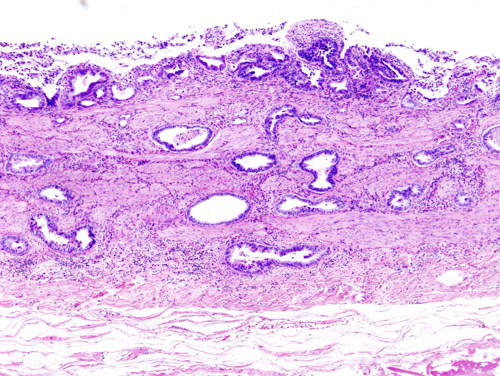

Chronic cholecystitis is characterized by the gallbladder mucosa herniating into the skeletal wall (Rokitansky-Aschoff sinus).

Porcelain gallbladder is a complication of late stage chronic cholecystitis.

Porcelain gallbladder is a shrunken, hard gallbladder because of chronic inflammation, fibrosis, and dystrophic calcification.

Porcelain gallbladder findings vastly increases the risk for carcinoma of the gallbladder.